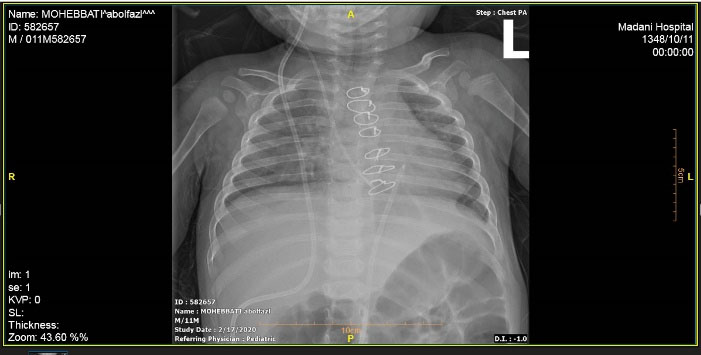

A male infant who underwent VP implantation due to congenital hydrocephalus at the age of 2-month-old presented with fever and lethargy at the age of 8-month-old. Pericardial effusion was detected in transthoracic echocardiography and plain chest radiography (), and he underwent pericardial window under general anesthesia and a mediastinal chest drain was implanted in the pericardial space. After draining the excessive pericardial fluid, the mediastinal chest drain was removed and the patient was discharged under appropriate conditions. The patient presented again at 11 months of age due to fever, lethargy, recurrent vomiting, and respiratory distress. In chest radiography migration of the distal end of VP catheter into mediastinum was suspected. More evaluation by transthoracic echocardiography (TTE) showed the entrance of catheter into right ventricle after perforating the diaphragm and pericardium. Meanwhile a mass lesion at tip of catheter was detected in favor of vegetation and endocarditis ().

Figure 2. Plain chest radiography depicting the entrance of VP shunt into the heart cavity (at the age of 11 month old).

The patient planed for open-heart surgery and all the necessary arrangements were made.(). Cardiopulmonary bypass was conducted under general anesthesia with a middle sternotomy technique and cannulation of the superior and inferior vena cava. The body was cooled to 30 °C and the cardiopulmonary solution was injected from the root of the heart aorta. In the right ventricle, a vegetation of 5 cm long was observed originating from the entrance point of the VP shunt and continuing up to the right ventricular outflow tract and the tricuspid valve. The vegetation was extracted and the tip of the VP shunt was directed back to the peritoneal cavity. The tricuspid valve was intact with appropriate function. The right ventricle and atrium were repaired and the patient was detached from cardiopulmonary bypass after warming up. Two drains were placed in the pleural space and one drain in the mediastinum and the sternum was closed. The patient was transferred to the intensive care unit (ICU) in stable condition and recovered after one day. Two weeks later, the patient was discharged in stable condition. Two weeks after discharge, the patient presented again with symptoms of vomiting, tachypnea, and lethargy. Chest X-ray and thoracic echocardiography revealed that the VP shunt was again migrated about 2 cm into the anterior mediastinum ( and ). The patient underwent reoperation under general anesthesia and the VP shunt was shortened and re-inserted into the peritoneal cavity. The patient was transferred to the ICU in stable condition and recovered after 6 hours. Antibiotic treatment was continued for six weeks and the patient was discharged in stable condition. In follow-up visits after two years, the VP shunt functioned well and no particular complication was observed.